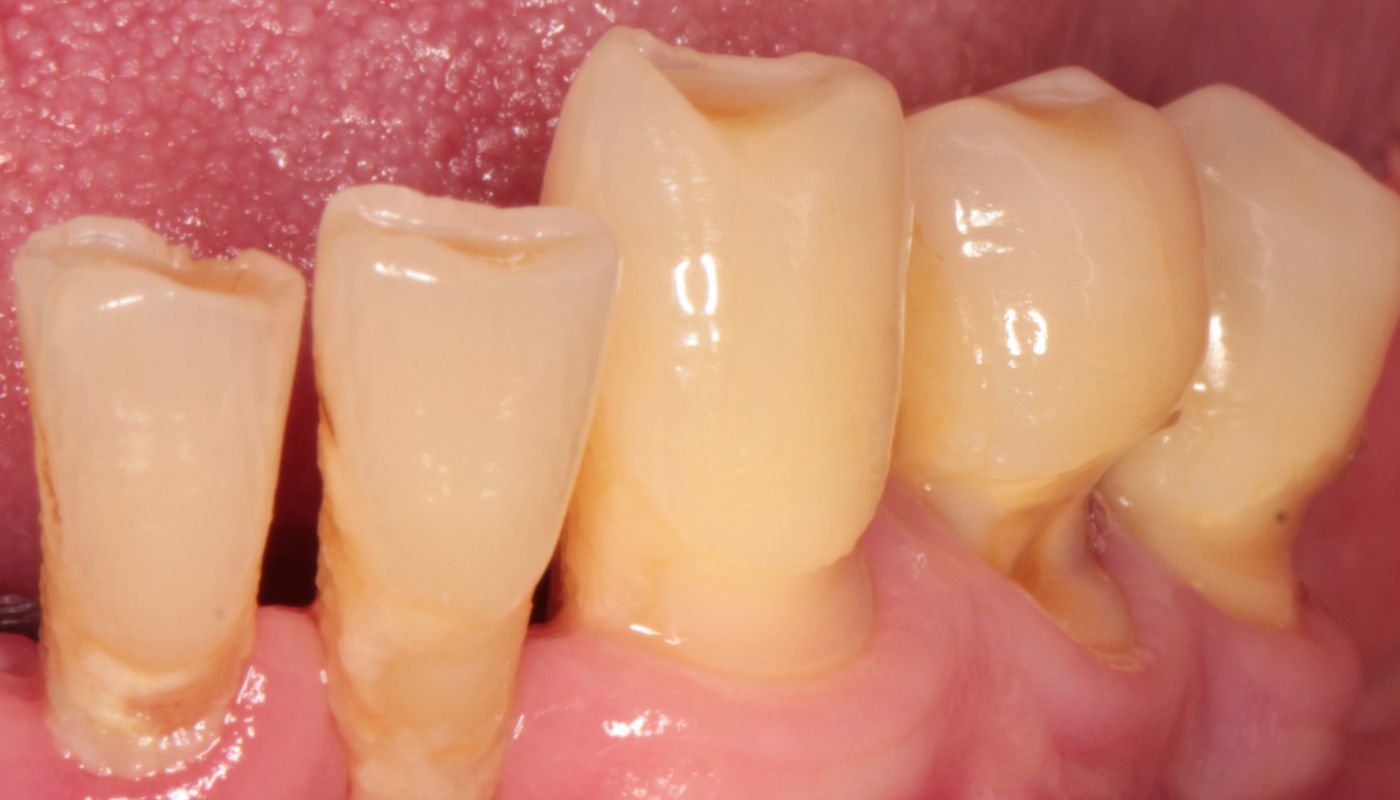

Odsłonięte szyjki zębowe narażone są większą adhezję (przyleganie) płytki nazębnej oraz osadzanie się kamienia. Dodatkowo, w wyniku niekorzystnej akumulacji płytki bakteryjnej oraz różnicy grubości szkliwa przy szyjce zęba w stosunku do korony, dochodzi bardzo często do zmian próchnicowych. Leczenie próchnicy w przypadku odsłoniętych szyjek jest obarczone dodatkowym ryzykiem powikłań (np. konieczność leczeni kanałowego). Wynika to z lokalizacji oraz bliskości miazgi.

Odsłonięcie szyjek zębowych, gdzie pojawia się stan zapalny, spowodowane jest nagromadzeniem się płytki bakteryjnej, która doprowadza do powstawania kamienia nazębnego. Nieleczona wiele lat choroba przyzębia, zwana paradontozą (z łac.periodontitis) powoduje trwałe zanikanie dziąseł i kości, a w konsekwencji odsłonięte szyjki oraz powierzchnie korzeni.

Niewłaściwa higiena zębów czy palenie papierosów stwarzają idealne warunki narastania płytki nazębnej na powierzchni zębów. Zalegające złogi nazębne stykając się z dziąsłami powodują ich drażnienie, przez co stwarzają podłoże do wytwarzania stanu zapalnego przyzębia. Dochodzi do obniżania się nasady zęba oraz odsłaniania szyjek zębowych.